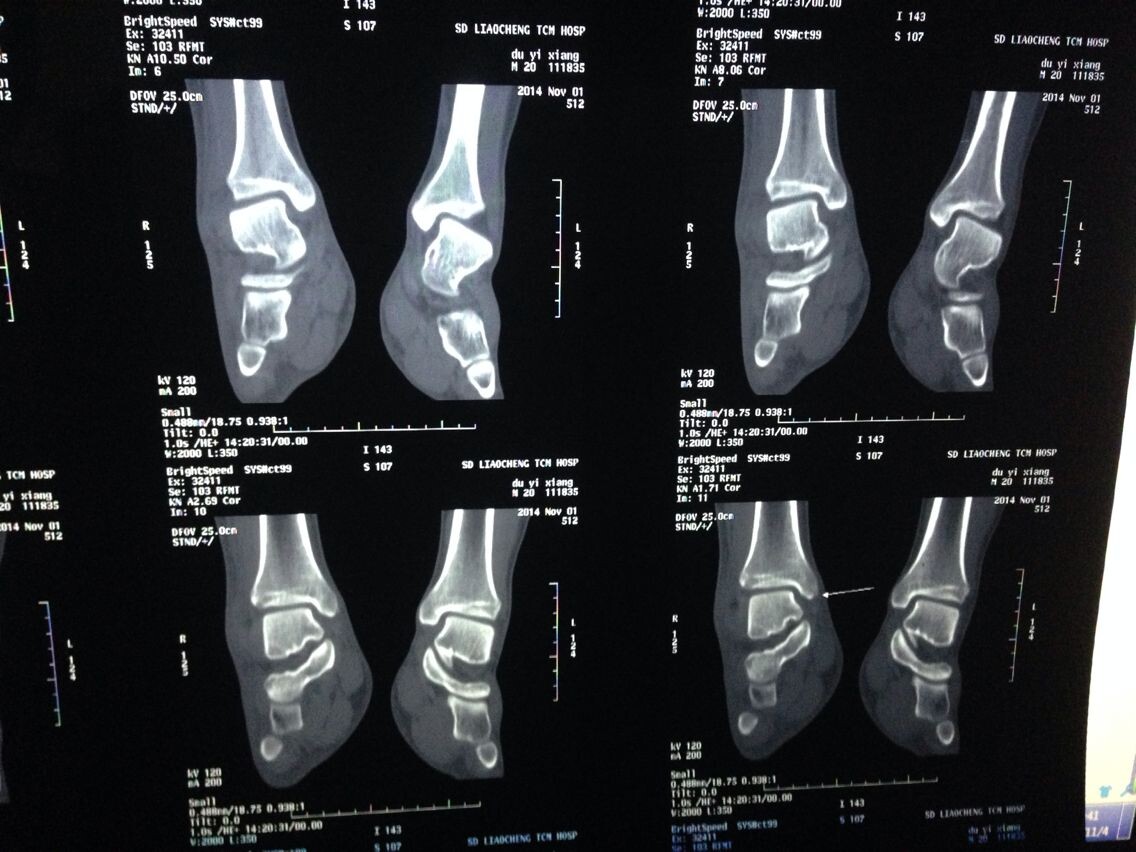

跪求看片啊。。。骨科。脚部

ct吧

谁能给我分析分析啊,,,,,医生也没说什么,有点敷衍

片子不全吧,顺序也很重要